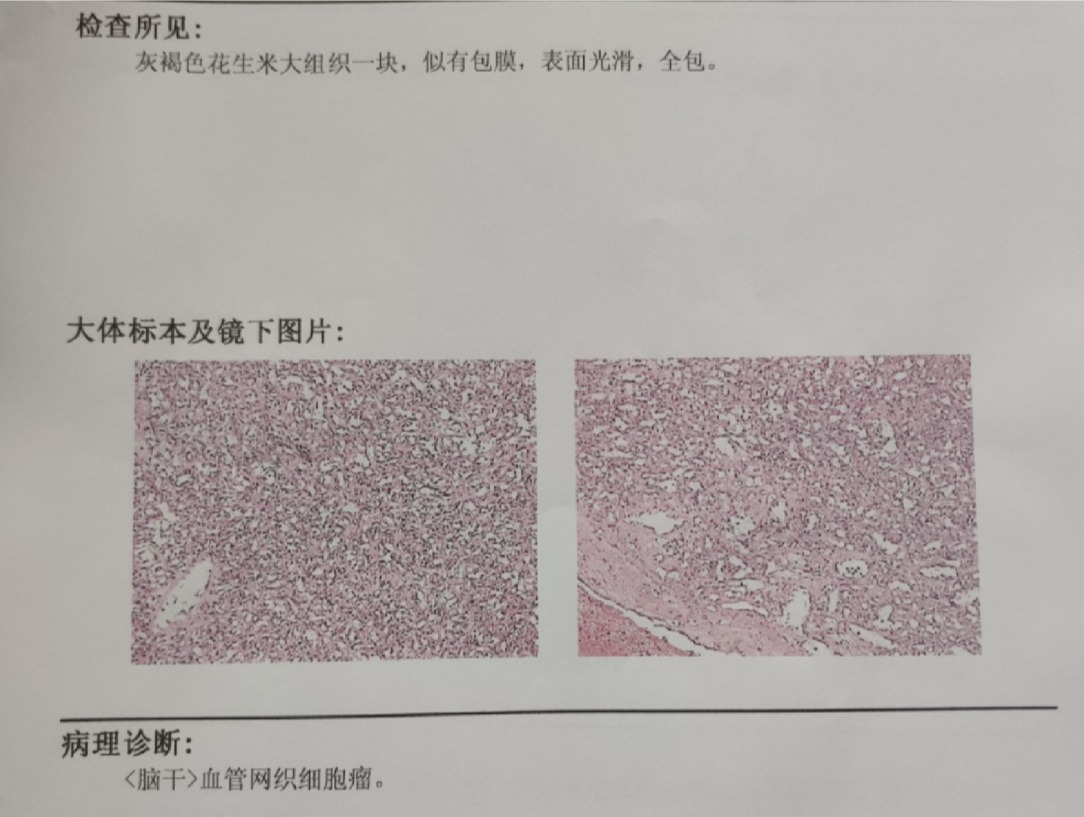

术后患者病理为血管网质细胞瘤。患者恢复良好,行走如常KPS评分90分出院。原先口角歪斜纹明显改善,肢体麻木明显减轻。